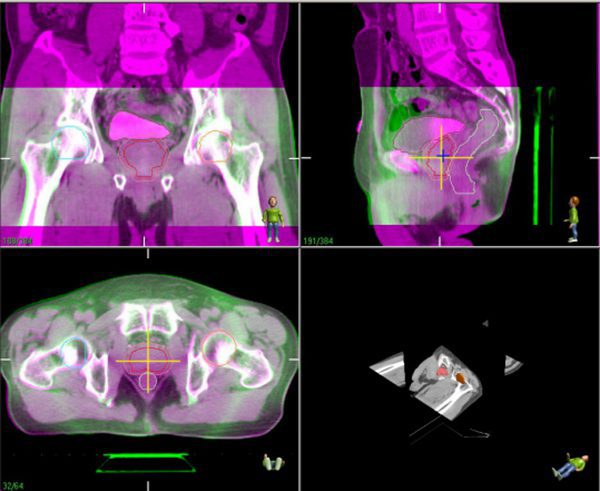

Physician-directed Image Guidance at treatment. At every treatment session, a pre-treatment scan is taken to determine the prostate position and its relationship with the neighbouring organs like the rectum and bladder. The physician is on-site to make positional adjustments to the treatment area to ensure full dose to the prostate and minimised dose to the rectum and bladder, as planned.

Imaging on-site at the treatment unit is superimposed over the planning CT, to ensure match of the prostate, rectum and bladder position according to plan